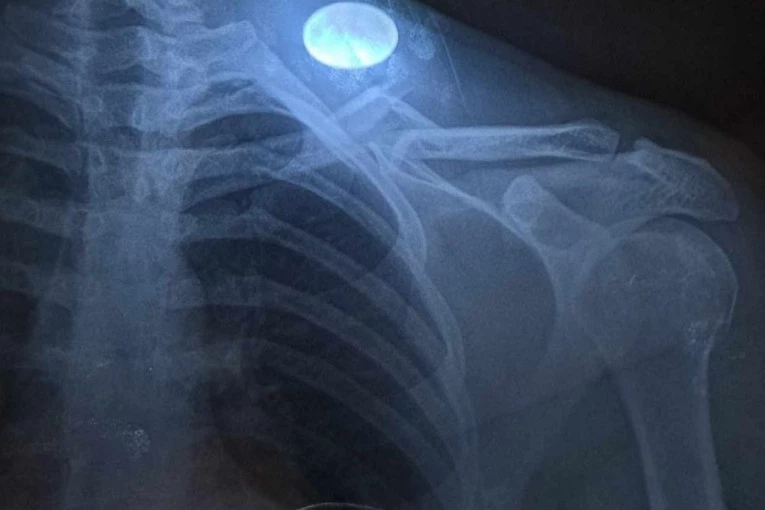

Međutim, kompletna utakmica ostala je u senci teške povrede gostujućeg fudbalera Petra Markovića koji je u 27. minutu morao da napusti igru, a dan kasnije njegov klub javnosti se obratio saopštenjem u kojem je javnost obavestio o stepenu povrede dvadesettrogodišnjeg fudbalera:

- Nakon detaljnih analiza i jutrošnjih pregleda, ponovljenog snimanja, naš prvotimac, Petar Marković pretrpeo je prelom ključne kosti na čak šest mesta. Odlukom uprave i predsednika kluba odlučeno je da se o jučerasnjim dešavanjima podnese kompletan izveštaj izvršnoj disciplinskoj komisiji.